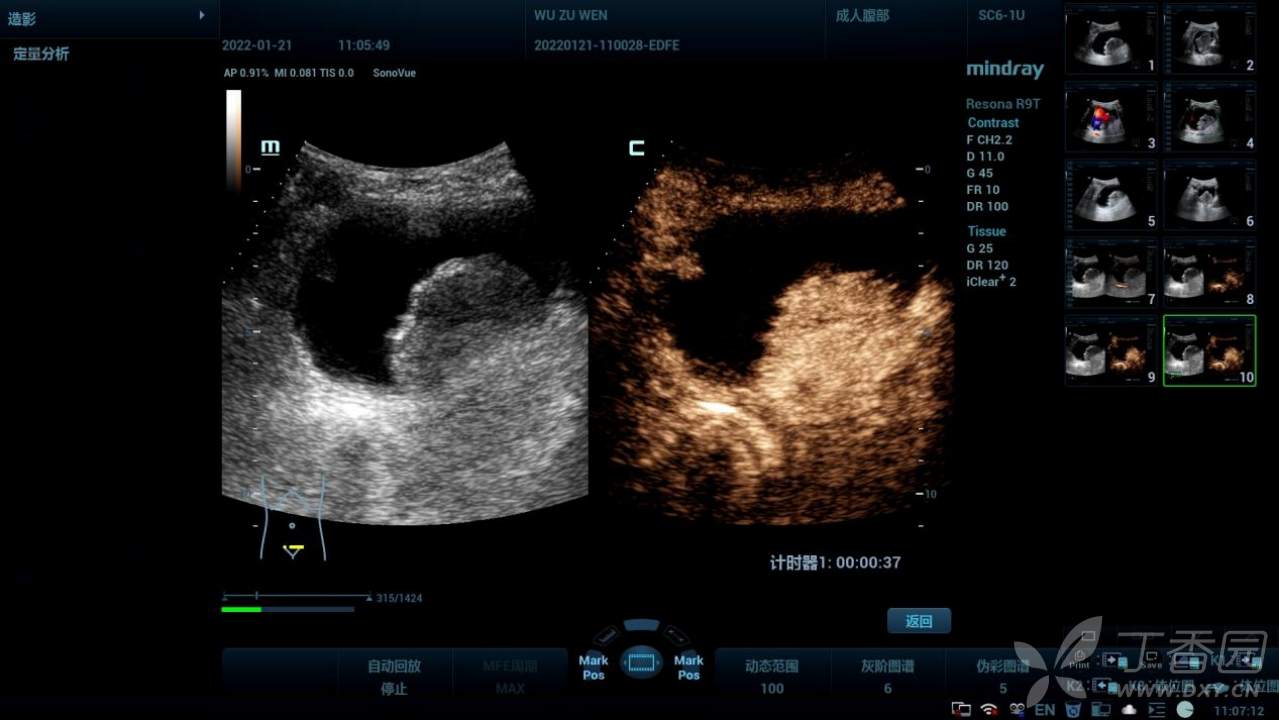

超声造影:

增强表现:动脉早期呈均匀高增强,动脉晚期均匀消退。